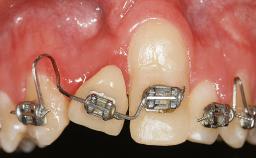

It is sometimes necessary to remove and replace compromised implants. This case is a clear example of the need for multiple steps to achieve an optimal therapeutic result for patients with non-salvageable implants. It illustrates how the lost soft and hard tissues were rebuilt in a sequence that improved the healing of the hard tissues and assured their long-term stability. The 35-year-old healthy patient presented with clinical attachment loss on the proximal and lingual surfaces of the natural dentition. Some gingival recession was present on natural teeth, particularly in the posterior sextants (S1, S3, S4, and S6).

Bone Augmentation Horizontal|Staged|Vertical

Soft Tissue Grafting Staged